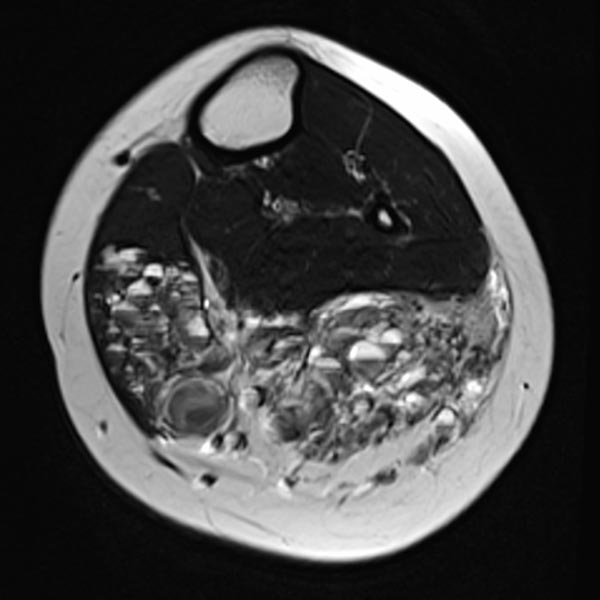

Axial T2-weighted MRI of the left lower leg shows multiple dilated, dysplastic veins in a venous malformation throughout the superficial flexor muscles. Slow flow causes stasis of the blood within the malformation with the formation of fluid-fluid levels. Almost the entire muscle consists of malformation and fatty tissue. Also visible is a large thrombus in a dilated, dysplastic vein.